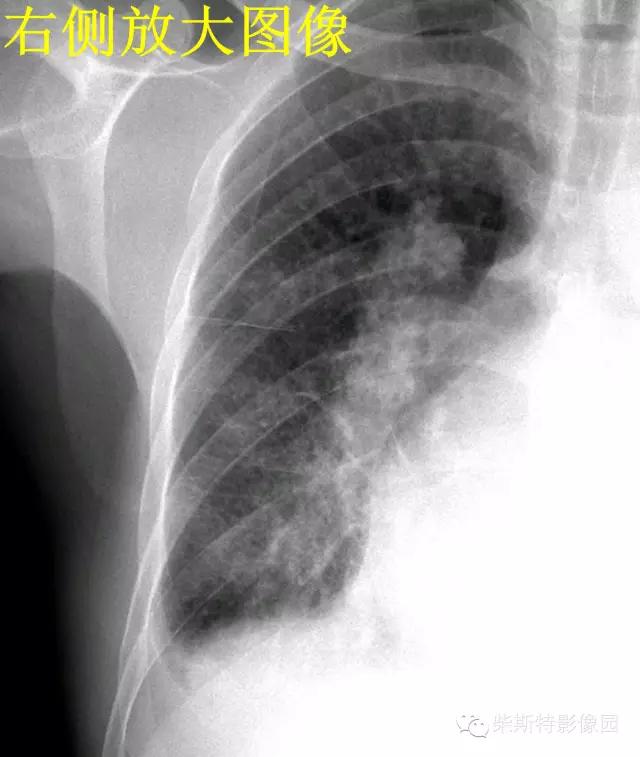

2.B线:为克氏线征中最常见者,表现为较短的不分又的梯状致密横线影,长不超过2cm,宽不超过1mm。常位于两下肺野的外带(肋隔角)平行的次出现,亦可见于中肺野,但从不出现于上肺野。其外端常抵达胸膜缘并与之垂直,以右侧为多见.